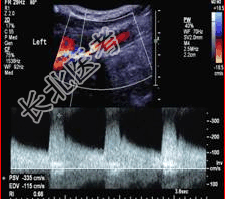

- [材料题] 患者男,59岁,因“右侧肢体麻木、无力,伴言语障碍及一过性意识丧失1个月”来诊。

- 简答题2、颅脑CT:未发现明显异常。颈动脉超声检查如下图。根据图像判断病变程度是什么?